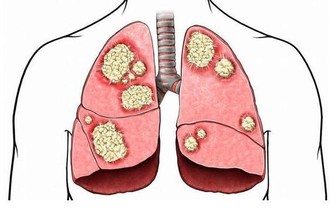

血糖開始升高,有虛火者此時表現明顯。陽虛、肺結核等患者的臉部最紅。